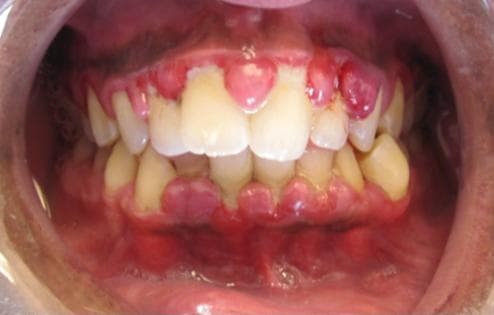

Gingivitis is a non-destructive disease that causes inflammation of the gums. The most common form of gingivitis, and the most common form of periodontal disease overall, is in response to bacterial biofilms (also called plaque) that is attached to tooth surfaces, termed plaque-induced gingivitis. Most forms of gingivitis are plaque-induced. While some cases of gingivitis never progress to periodontitis, periodontitis is always preceded by gingivitis. Gingivitis is reversible with good oral hygiene; however, without treatment, gingivitis can progress to periodontitis, in which the inflammation of the gums results in tissue destruction and bone resorption around the teeth. Periodontitis can ultimately lead to tooth loss. The symptoms of gingivitis are somewhat non-specific and manifest in the gum tissue as the classic signs of inflammation: Swollen gums Bright red gums Gums that are tender or painful to the touch Bleeding gums or bleeding after brushing and/or flossing Bad breath (halitosis) Additionally, the stippling that normally exists in the gum tissue of some individuals will often disappear and the gums may appear shiny when the gum tissue becomes swollen and stretched over the inflamed underlying connective tissue. The accumulation may also emit an unpleasant odor. When the gingiva are swollen, the epithelial lining of the gingival crevice becomes ulcerated and the gums will bleed more easily with even gentle brushing, and especially when flossing. Recurrence of gingivitis Periodontitis Infection or abscess of the gingiva or the jaw bones Trench mouth (bacterial infection and ulceration of the gums) Swollen lymph nodes Associated with premature birth and low birth weight A study from 2018 found evidence that gingivitis bacteria may be linked to Alzheimer's disease. Scientists agree that more research is needed to prove a cause and effect link. "Studies have also found that the bacteria P. gingivalis – which are responsible for many forms of gum disease – can migrate from the mouth to the brain in mice.